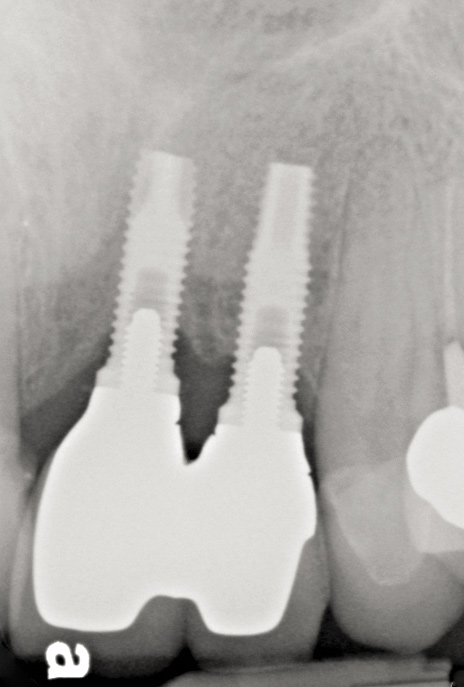

Problem: Implants are placed with insufficient inter-implant distance in the esthetic zone with significant bone loss (Figure 49 through Figure 51).

Fig 49. Clinical presentation of implants that were placed with insufficient inter-implant distance. Forced eruption would not have been appropriate in this situation because the interproximal biologic width was violated.

Fig 50. Note the lack of interproximal papilla height between implants Nos. 9 and 10.

Fig 51. Radiograph of implants placed with insufficient inter-implant distance in Figure 49 and Figure 50 with attachment loss.